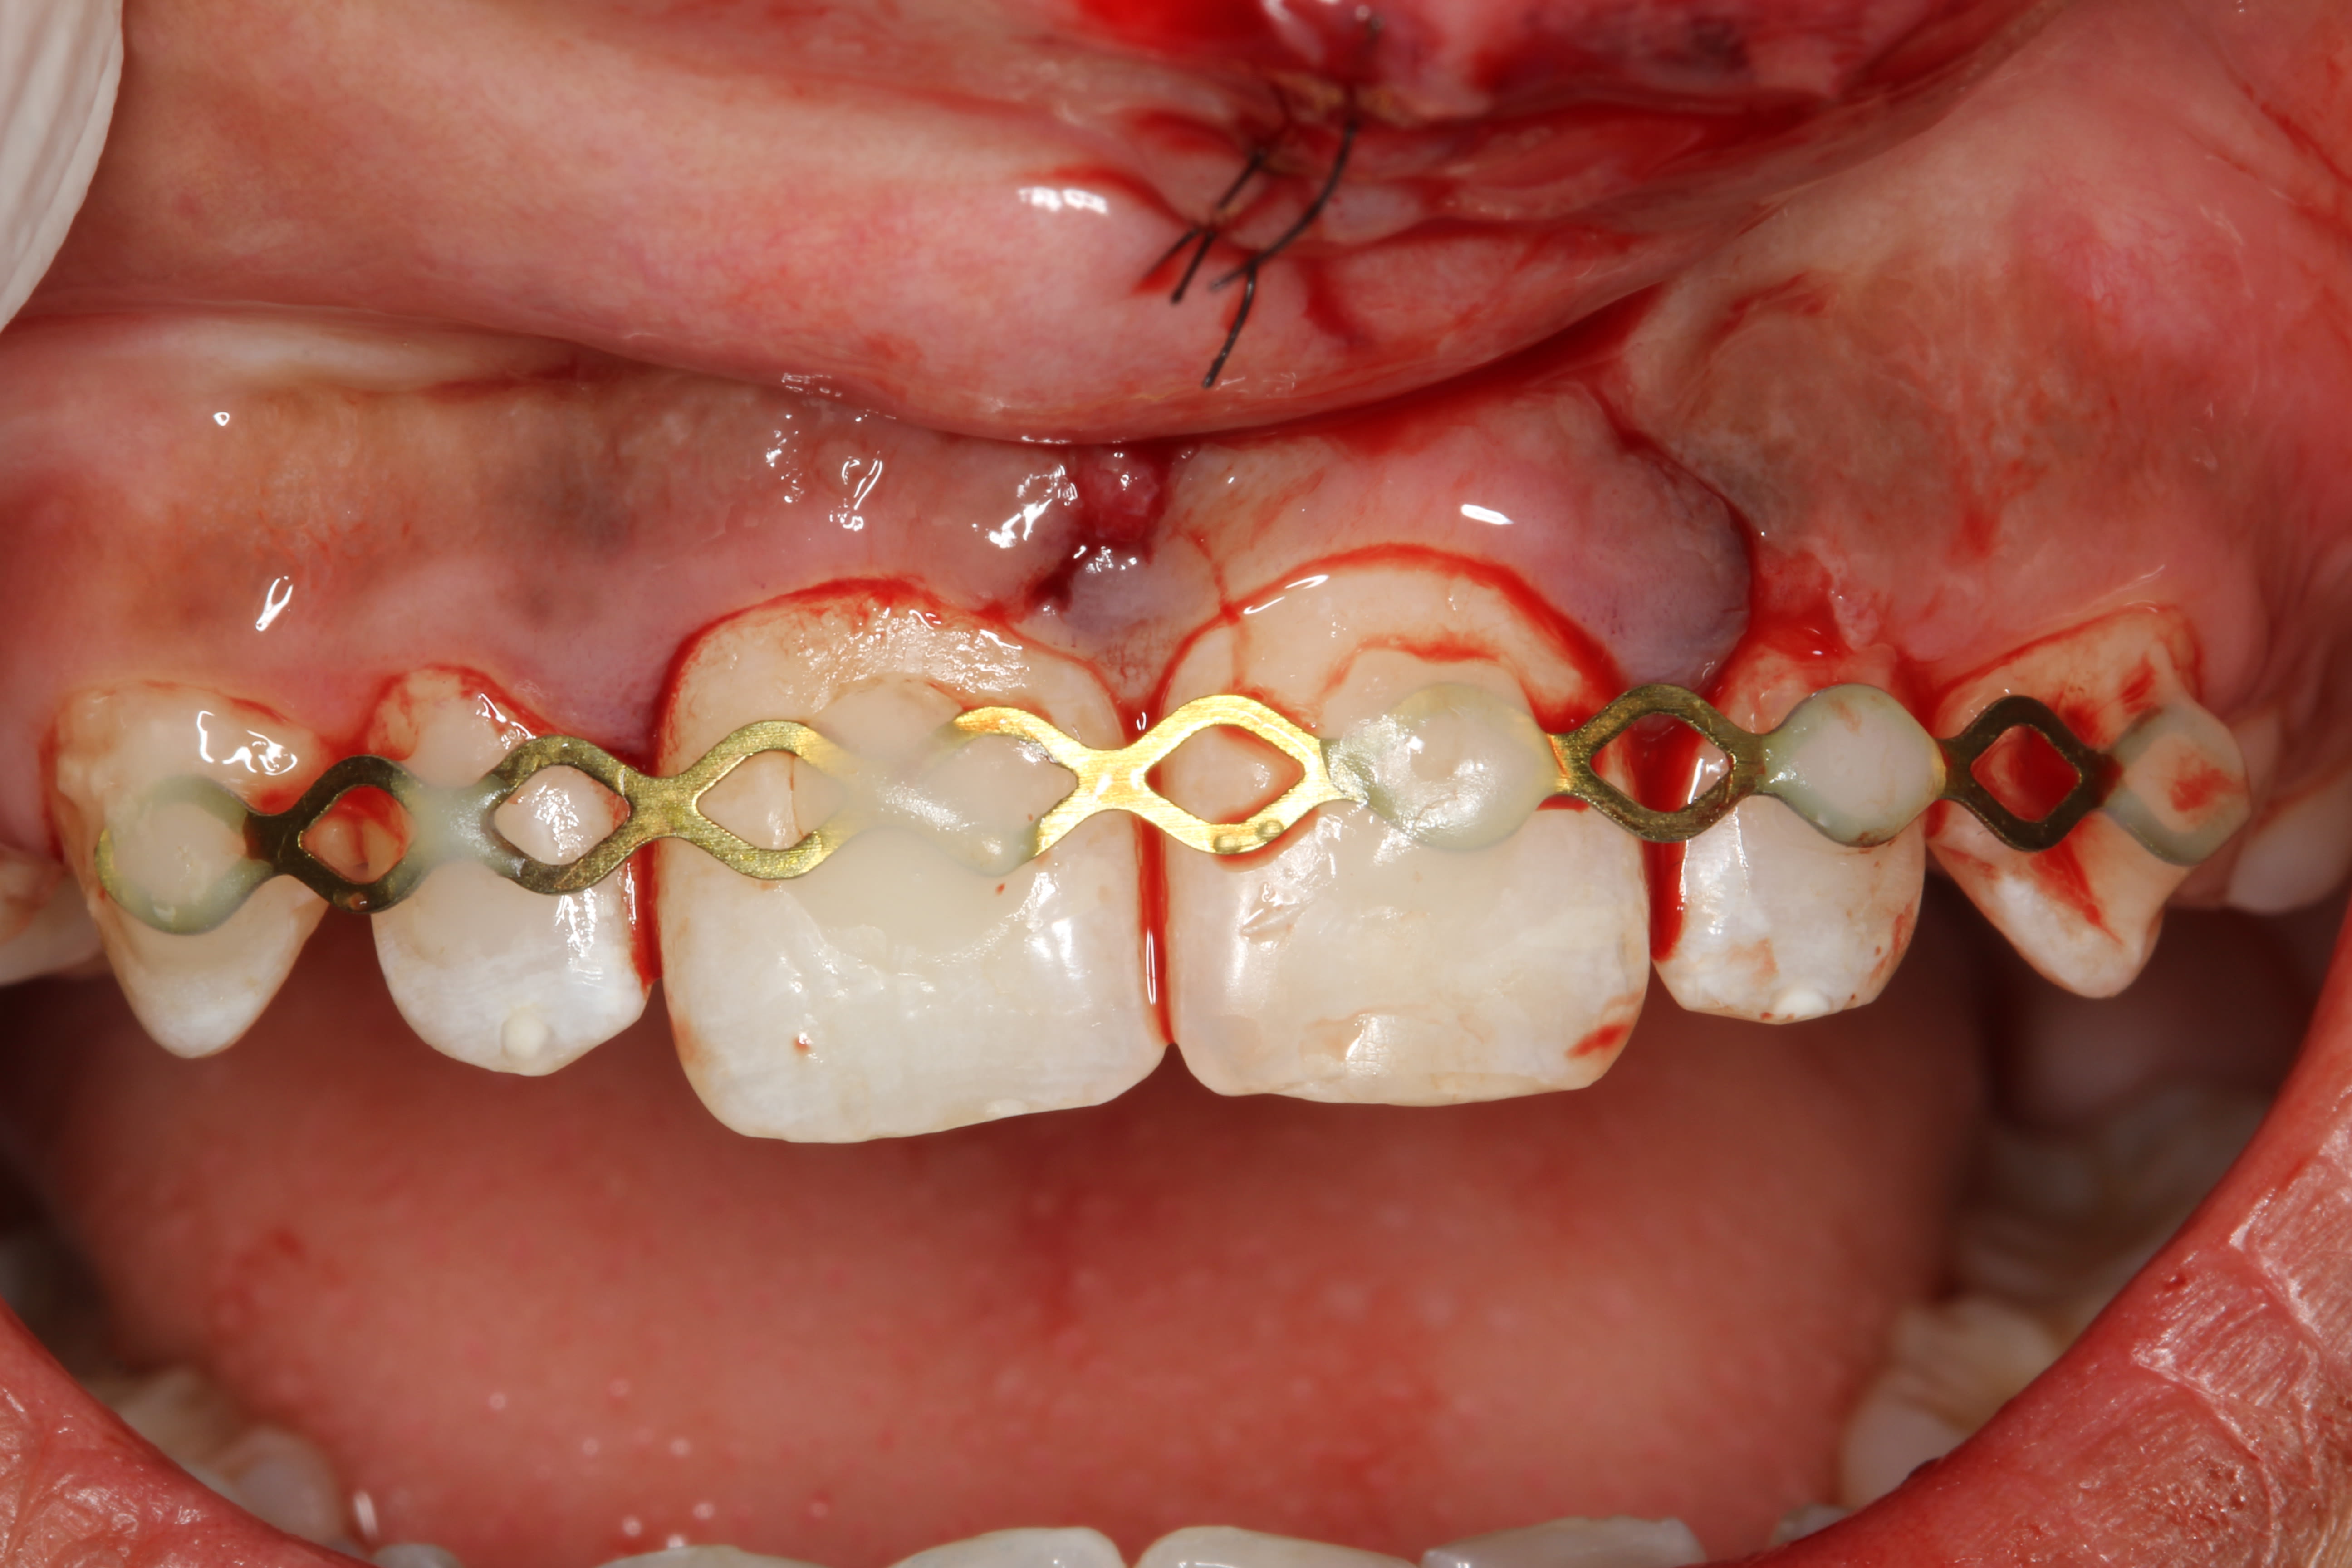

- contention souple de 13 à 23

- suture de la lèvre

par contre je met un fil tressé, c plus souple et plus hygiénique et je prolonge la durée de contention. 15 jours c'est limite pour une expulsion.